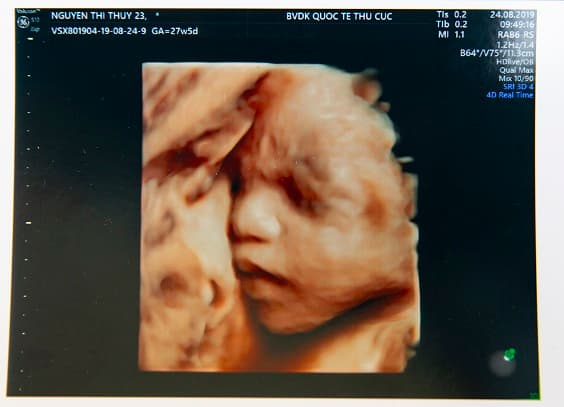

Trên kết quả siêu âm thai, thông thường chúng ta sẽ nhìn thấy rất nhiều ký hiệu được viết tắt. Đây được gọi là những chỉ số siêu âm của thai nhi. Việc tìm hiểu và nắm vững thông tin đó là vô cùng quan trọng. Từ đây mẹ sẽ có thể đánh giá được sự phát triển của thai nhi một cách toàn diện. Một số chỉ số bao gồm: Đường kính lưỡng đỉnh, chiều dài đầu mông, chiều dài xương đùi, số cân nặng của thai nhi…

Chỉ số siêu âm thai nhi giúp mẹ đánh giá được sự phát triển của thai nhi một cách toàn diện